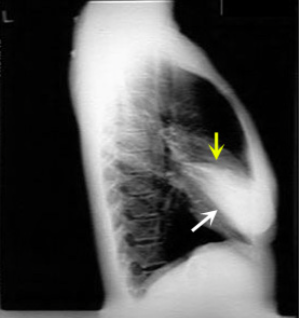

What is this consolidation?

RML Consolidation